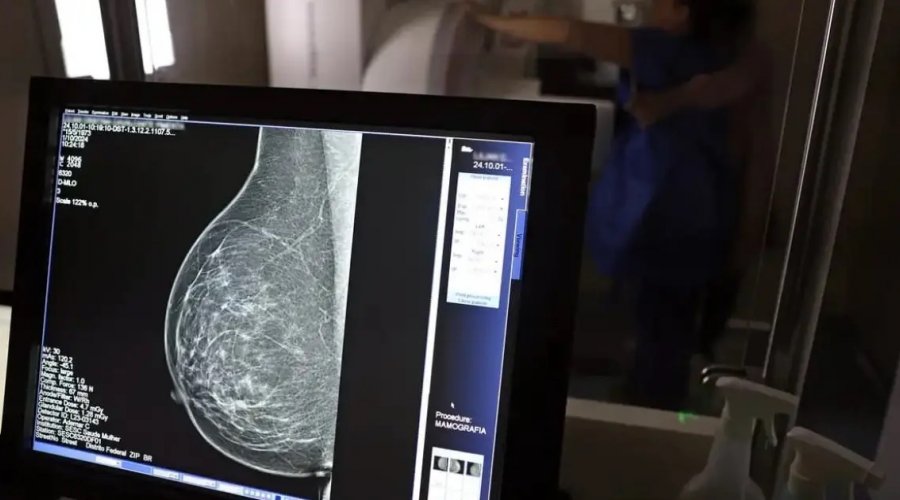

Foto: José Cruz / Agência Brasil

A Superintendência de Estudos Econômicos e Sociais da Bahia (SEI) divulgou o relatório Info Câncer de Mama 2025, que atualiza os dados sobre a doença no estado. O levantamento estima 4,3 mil novos casos em 2024 — uma taxa de 43,8 por 100 mil mulheres. Em Salvador, o número é ainda maior: 64,3 por 100 mil.

O câncer de mama segue como o tipo mais letal entre as mulheres baianas, representando 16% de todas as mortes por neoplasias malignas no estado, com 1,4 mil óbitos registrados em 2024. A taxa de mortalidade foi de 17,5 a cada 100 mil mulheres.